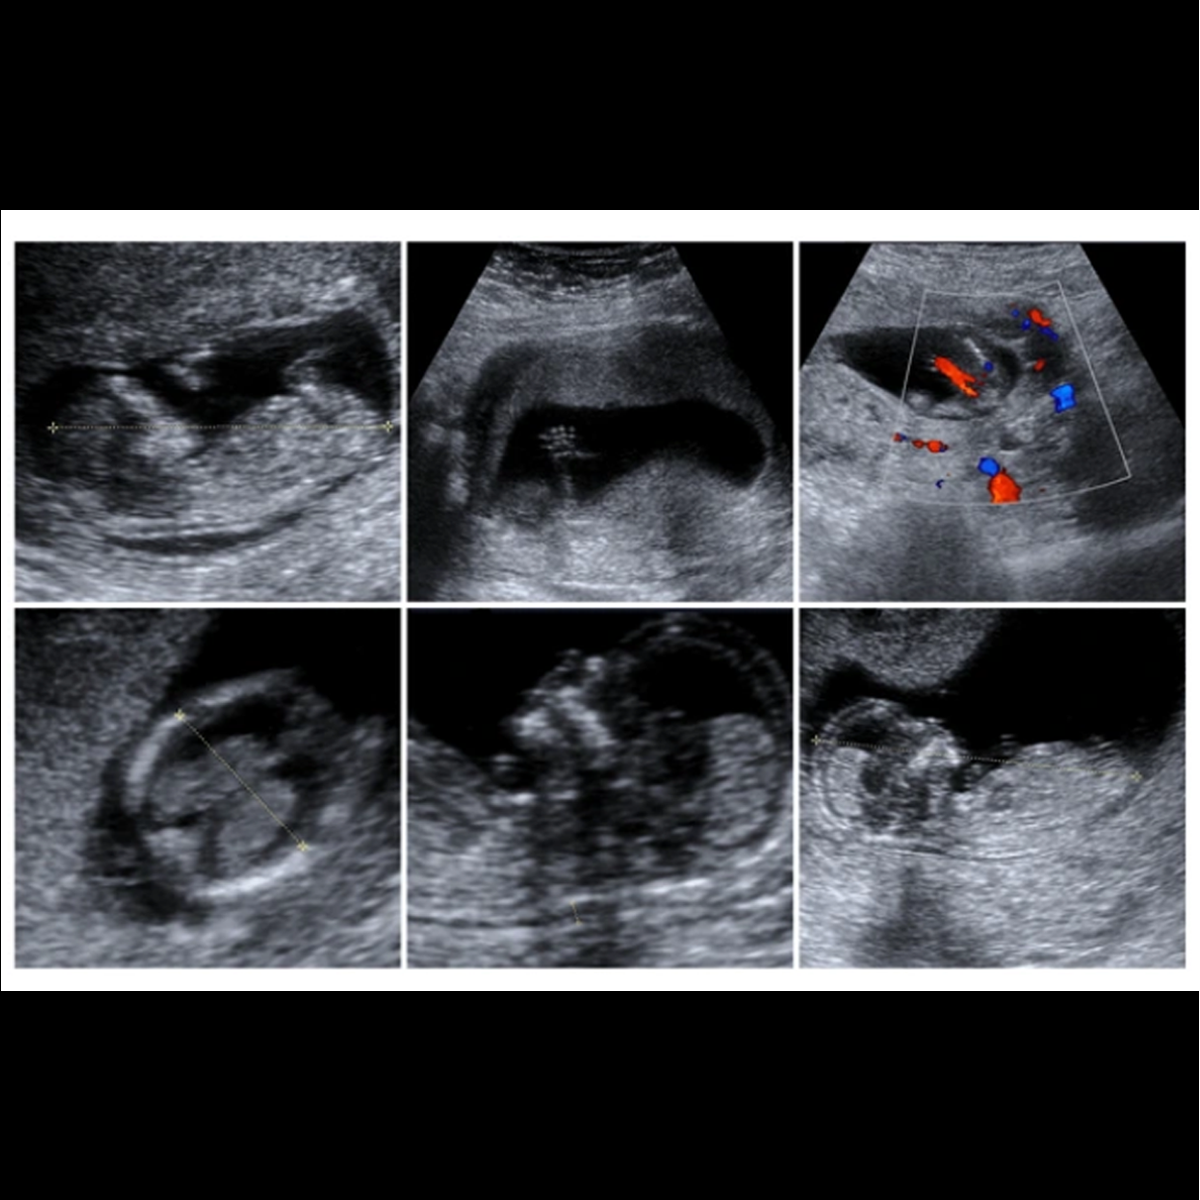

I. Viability scan (6-10 weeks):

This scan is done between 6-10 weeks of gestational age, to look for site of pregnancy, number of babies, size and cardiac activity.

II. First Trimester Screening for Aneuploidies / Anomalies / Pregnancy Complications (Done between 11- 13+6 weeks / 45- 84mm CRL):

This is the most important scan in pregnancy, which provides information on preventable complications in pregnancy, like preterm delivery and hypertensive disorders in pregnancy. If picked up at right time, these problems can be prevented. Screening involves scan and a blood test – to measure hormones free b-HCG and PAPP-A. Also, more than 60%of major structural defects and 93% of chromosomal problems can be identified at this time. Babies with Down syndrome (Trisomy 21, most common chromosomal problem) have intellectual delay and first trimester screening is the most costeffective and efficient way of screening all pregnant ladies for Down syndrome.